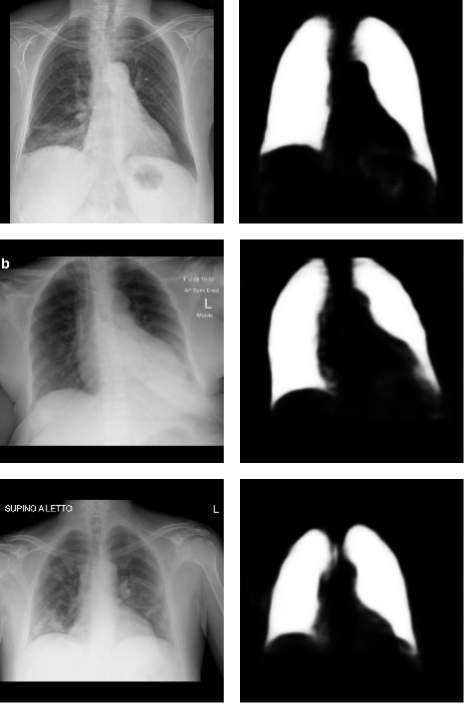

We ended up with 0.864 mean intersection over union in the test dataset. We analyzed the generated masks and found that they correctly indicated the lung areas. Most of the DNN mistakes were generating brighter regions in the gastric bubble area and in the lung region behind the heart. You can see examples of the generated masks, created with Covid-19 X-rays, in Figure 1.

Refer to caption

Figure 1: Examples of masks (created by the U-Net) and the corresponding Covid-19 X-rays. The images were gathered from the segmentation test dataset. From top to bottom, they represent a 70-year-old female on the first day of Covid-19 symptoms, a 67-year-old female on day 8 of symptoms, and a 40-year-old male on day 10.